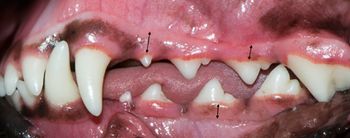

DEK Bulldogs, Labrador retrievers and beagles are prone to it. Why, what is it, and what can be done?